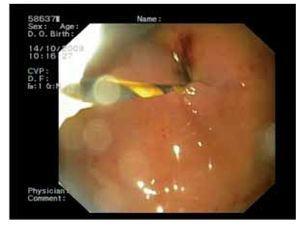

¿ Figure 2. Endoscopic view of the gastric fistulary orifice which is teared after the efforts made to insert the covered SEMS through the liver parenchyma. The endoscope is inserted over the wire which enters transgastrically the left bile duct exiting through the papilla and the duodenal SEMS, and comes out through the mouth after the Rendez-vous procedure.

A 43 year-old male with unresectable pancreatic head adenocarcinoma diagnosed 3 months before, was admitted because of incoercible vomiting and jaundice (bilirrubin level of 9.4 mg/dL). Gastroscopy showed tumoral infiltration of the duodenal bulb which prevented access to the ampulla. After informed consent process in which we discuss with the patient the available options including EBPD, another endoscopic session was planned in order to treat both digestive and biliary obstructions. Anticipating that EBPD could be necessary, the patient was placed in supine position under sedation with propofol. We started the procedure by deploying of a 14 cm long self-expandable enteral metallic stent (SEMS) (Hanarostent, Sewoon Medical, Korea) through the duodenal stenosis. After placing the duodenal stent we tried to access the second duodenal loop through the stent, but the stenosis was only partially dilated and we could only reach the superior duodenal flexure. This persistent stenosis despite the SEMS prevented us from attempting to perform ERCP. Thus, we inserted a linear array echoendoscope (Pentax 3630) into the stomach on a straightened position. We scanned the left liver lobe until a dilated bile duct near the liver surface was identified and targeted with a 19 gauge needle (Echo-Tip, Wilson-Cook medical, Inc., Winston-Salem, North Carolina, USA) which we inserted through the gastric wall. We performed an antegrade cholangiography confirming intra and extrahepatic bile duct dilation reaching the intrapancreatic portion, where a 4 cm long stenosis was observed. A 0.35 guide wire was inserted through the needle, and we could gain access through the papilla and made progress with the guide wire into the distal duodenum. After removing the needle, while leaving the guide wire in place, a 7 Fr plastic dilator catheter was introduced over the wire into the distal bile duct and duodenum. Once the fistula was dilated, we tried to insert a 6 cm long partially covered biliary SEMS (Wallstent, Boston Sci, Nattick, MA, USA) through the liver parenchyma with no success, despite repetitive attempts by changing the endoscope angulation. Since we had the distal end of the guide wire in the duodenal lumen, we removed the echoendoscope while leaving the guide wire in place, and inserted a frontal view endoscope through the previously placed duodenal stent until we reached the upper duodenal flexure, from where we could see the guide wire exiting the papilla and forming an intraduodenal loop. We grasped the distal end of the guide wire and extracted it through the mouth, performing an endoscopic rendezvous technique. Once we had both ends of the guide wire coming out through the mouth, we inserted the endoscope over the transgastric portion of the guide wire until we reached the gastric lumen. A 5 mm perforation originated in the parietal fistula with evident pneumoperitoneum was detected after air insufflation (Figure 1 and 2). In view of this situation, we decided to insert a transgastric partially covered SEMS communicating the left bile duct and the gastric lumen, in order to treat the biliary occlusion and seal the gastric perforation. Using now the frontal view endoscope and slightly pulling both ends of the guidewire, we were able to easily insert and deploy an 8 cm SEMS (Wallstent, Boston Sci, Natick, MA, USA) sealing the gastric perforation (Figure 3) and confirming bile flow to the stomach. Immediately after the exploration the patient referred mild abdominal discomfort which eased in a few hours. Twenty four hours later the patient was asymptomatic and a plain abdominal x-ray showed persistence of pneumoperitoneum. He resumed oral feeding with good tolerance 72 hours after the endoscopic procedure and was discharged asymptomatic seven days later with a bilirubin value of 2.4 mg/dL.